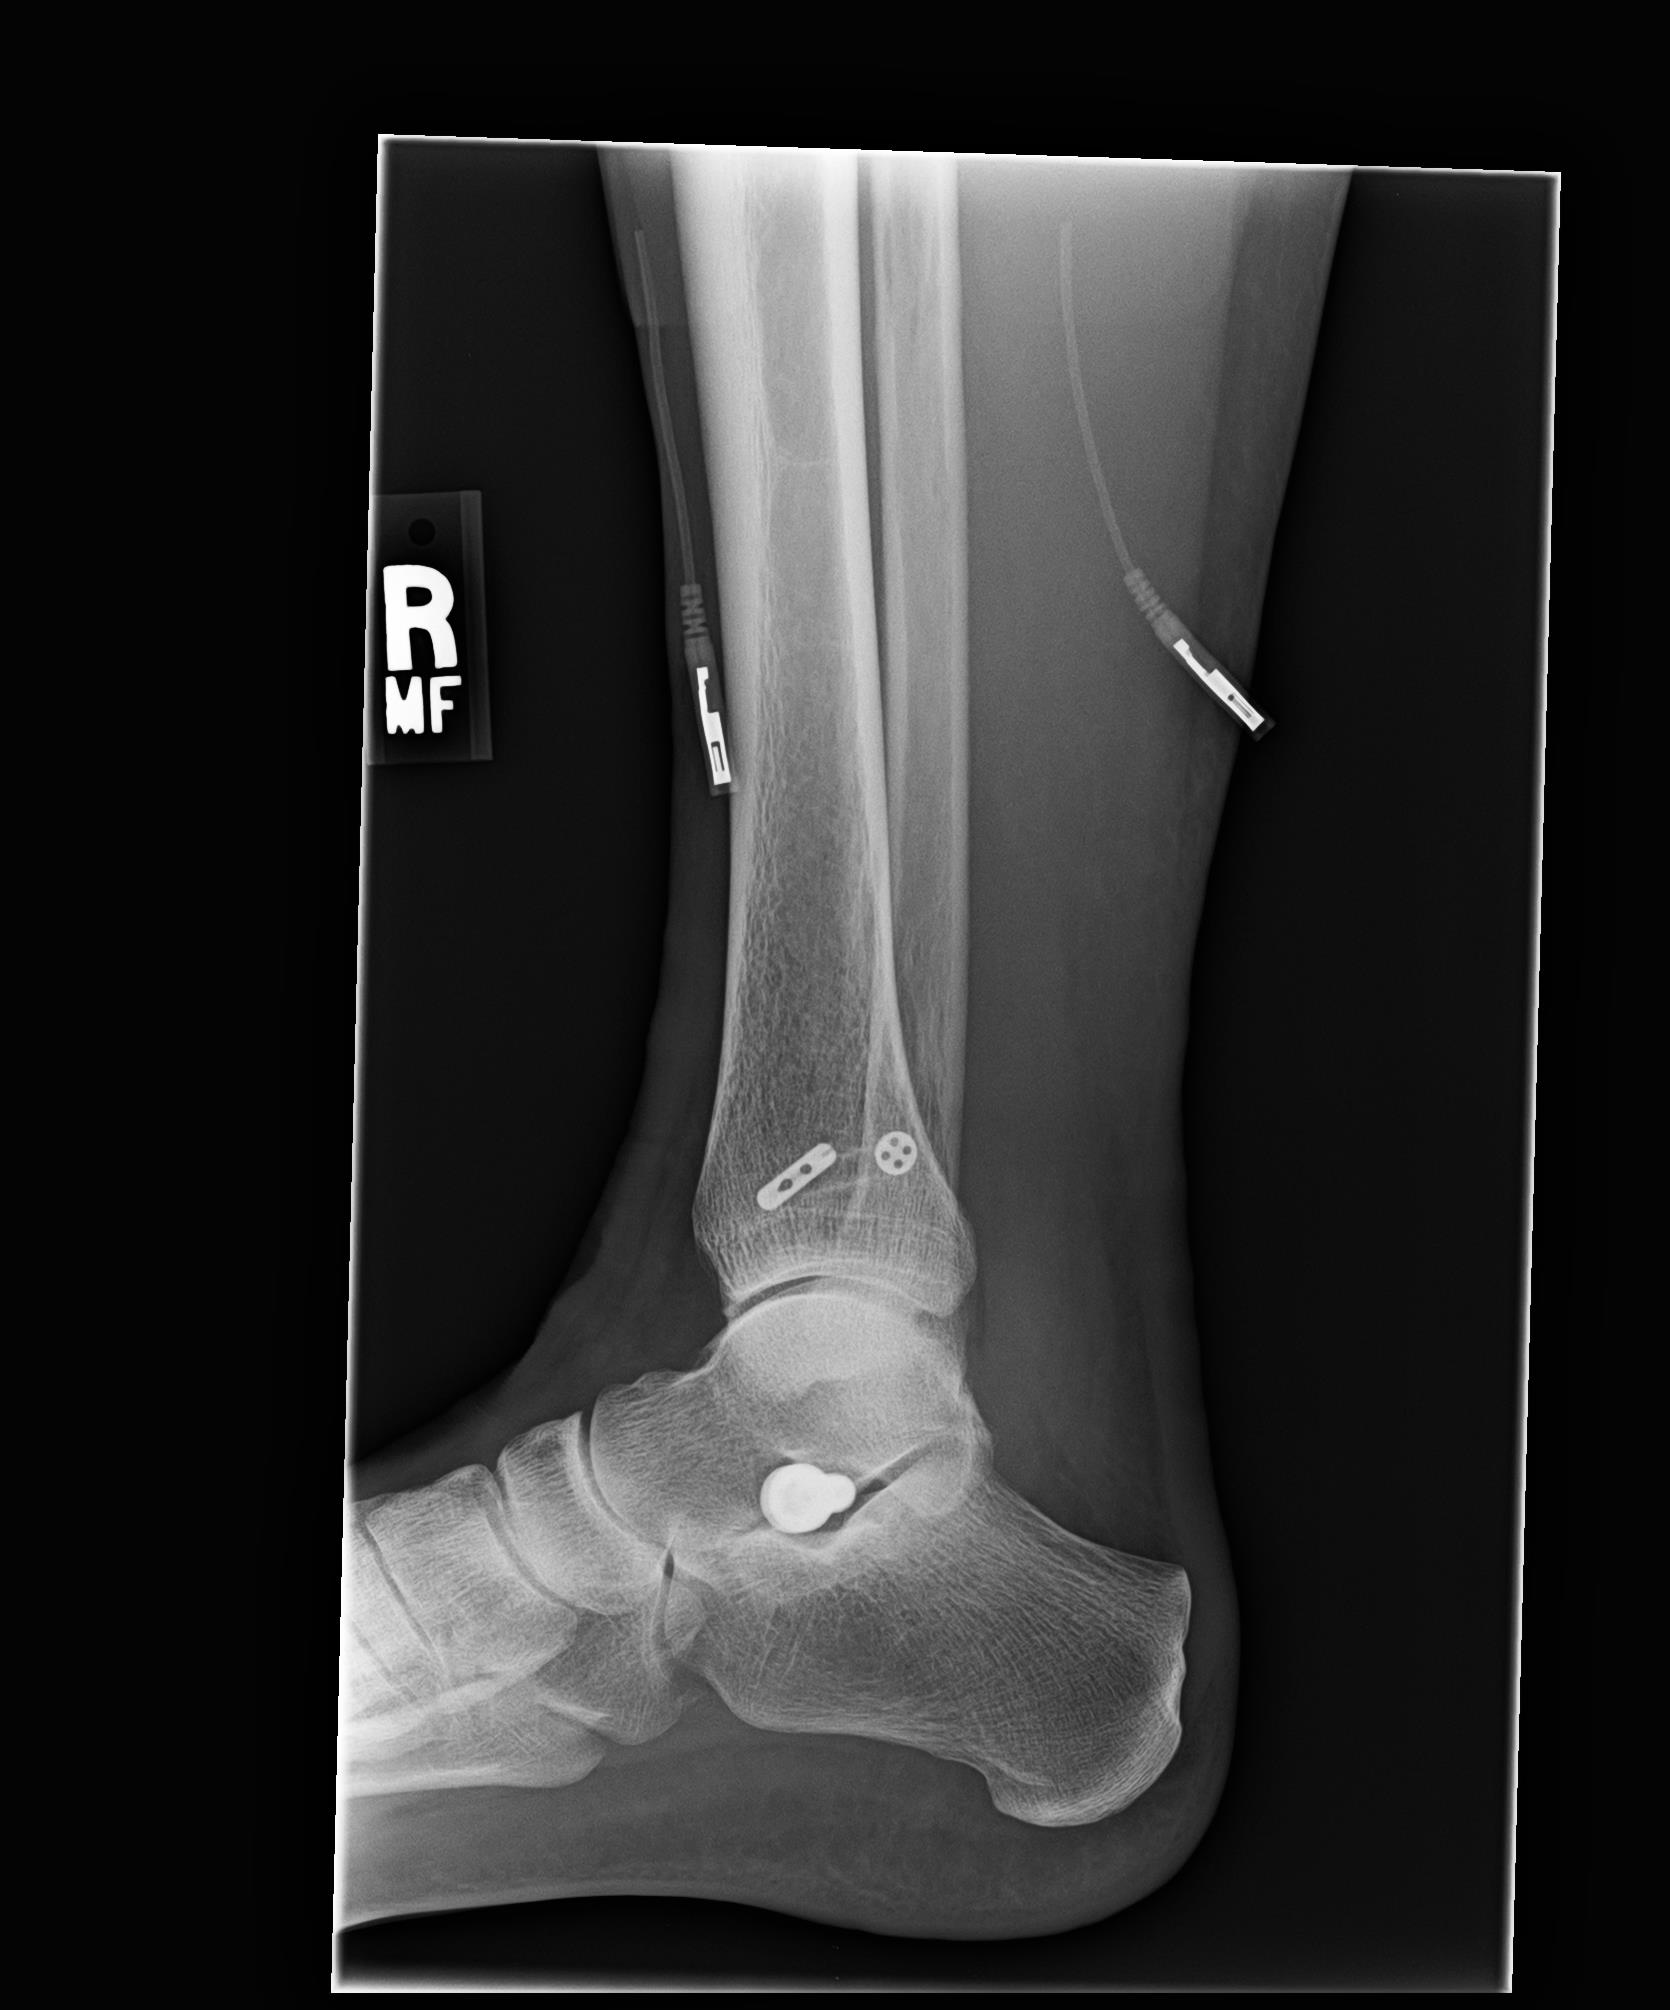

Ankle syndesmosis w/fractured fibula and ripped deltoid. Have tightrope and plate and screws Tightrope Plate Hole fibular buttress plate with two knotless syndesmosis tightrope implants. [1] tightrope® is a viable alternative to screw fixation for syndesmosis. The syndesmosis plate improves reduction and fixation by. Tightrope™ fixation for ankle syndesmosis. Syndesmosis surgery with tightrope fixation uses a wire, which when tensioned and positioned against the tibia and fibula, correctly aligns and stabilizes. It can be used. Tightrope Plate.